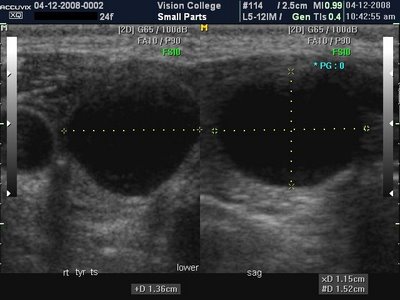

갑상선 낭포는 일반적으로 수류를 말하며 결절은 단단한 형태의 종괴를 말합니다.물집의 경우 비교적 부드럽고 양성질환일 가능성이 높으므로 통증이나 호흡곤란 같은 특별한 증상을 일으키지 않으면 경과를 지켜보는 것만으로도 충분합니다.

다만 갑상선 양성낭종의 크기가 커지거나 혹으로 인해 갑상선 조직 일부가 압박되어 통증, 호흡곤란, 연하장애 등이 있는 경우에는 수술적인 방법을 제거받는 방법도 고려해야 합니다. 통상 갑상선 양성 낭종의 크기는 1~3cm 정도이며,

작은 경우가 많아요. 일부는 4~6cm 이상에서 큰 낭종이 발견되는 경우도 있지만, 이 경우 크기가 작은 것은 아니기 때문에 정기적인 추적 관찰을 통해 결절 크기가 증가하지 않는지 확인해야 합니다. 물 또는 시간이 지남에 따라